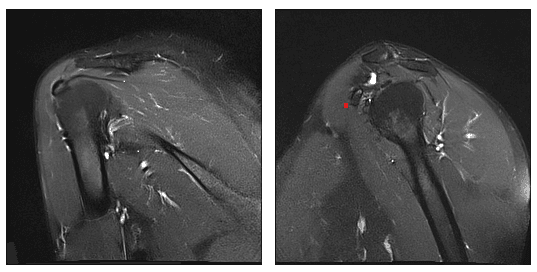

Vizualizare prin examinare RMN a calcificării în tendonul supraspinos